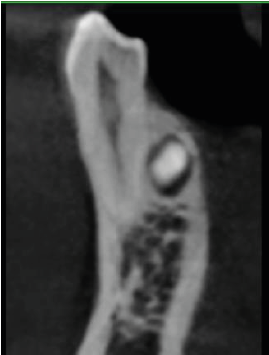

The crown of the supernumerary tooth is impacted against the middle third of the root of LR4 (44) (image 4a), while both the crown and root are in contact with the middle and apical thirds of the root of LR5 (45) (image 4b). There is no root resorption seen on LR4 (44) or LR5 (45).

4. Mesio-distal cross-section through LR4 and LR5 roots, showing the crown of the supernumerary lingually.

a. Through LR4 root, with part of the crown of the supernumerary lingually